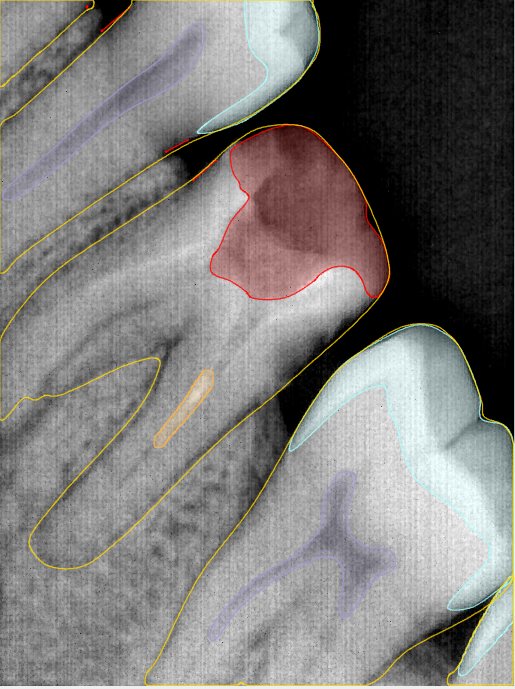

CR/DR 牙齿分割阶段记录

当前进展

- 完成了 CR/DR 牙齿相关分割训练

- 当前结果已经达到阶段预期,但仍有细节问题需要继续处理

相关测试

遇到的问题

- 训练过程中出现过 mask 下移问题

- 部分结果会出现 box 填充异常

- mask 边缘仍然有比较明显的锯齿感